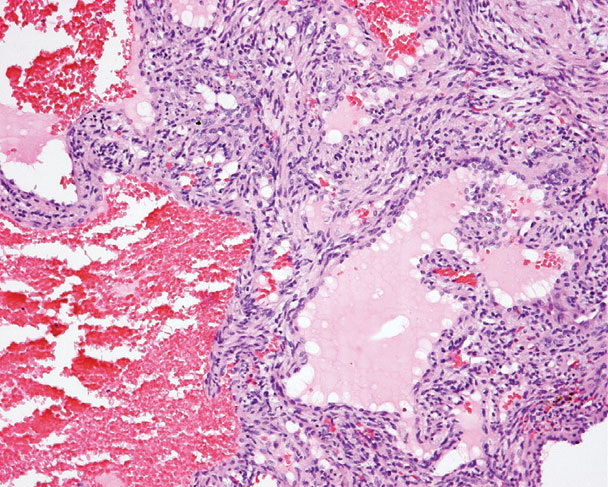

Spindle cell hemangioma = وعاؤوم مغزلي الخلايا